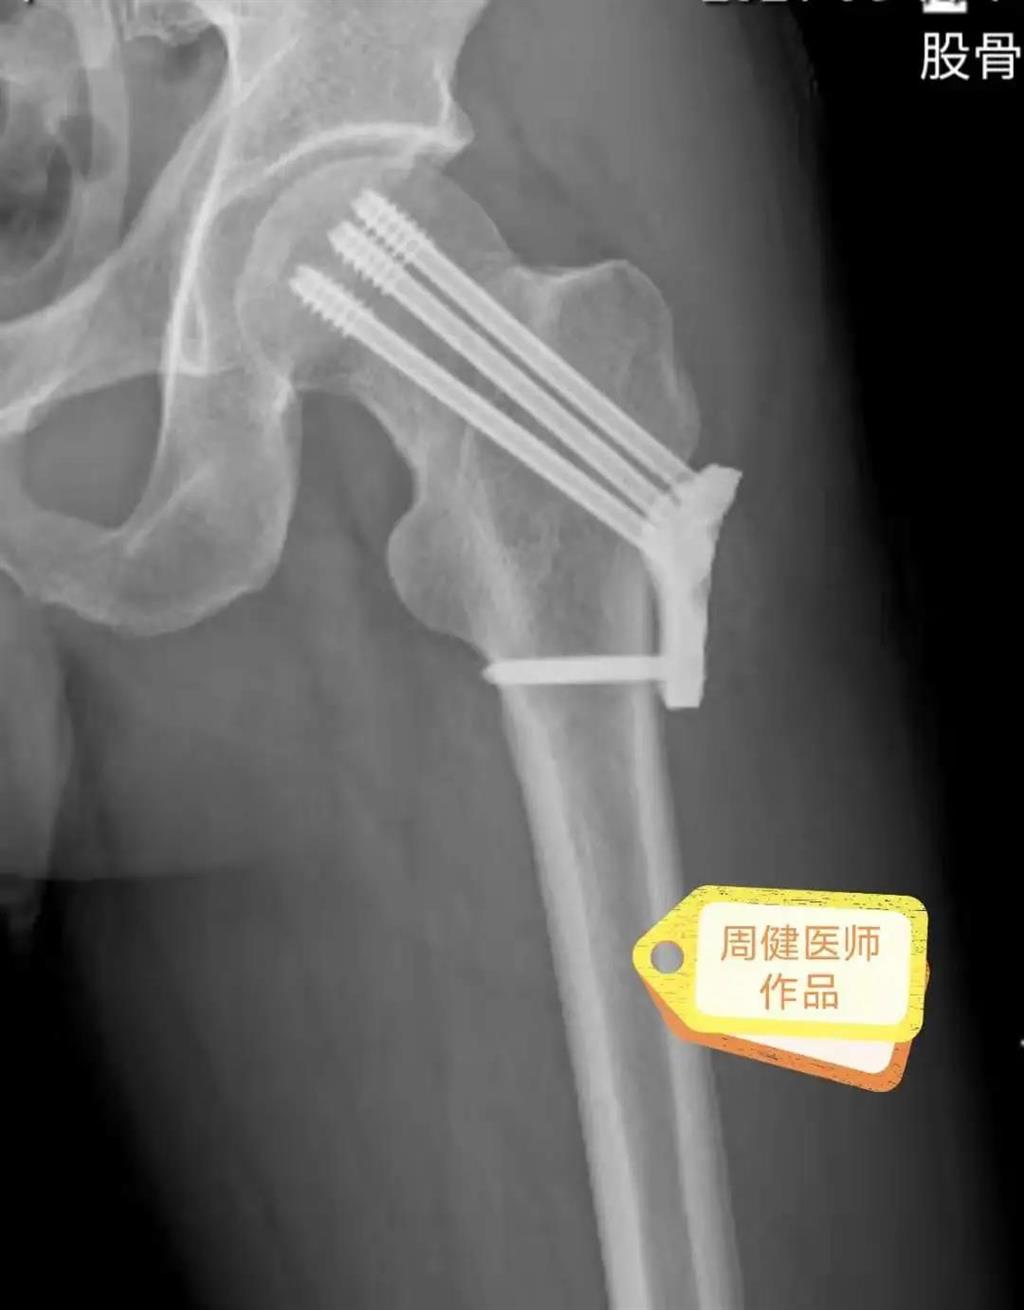

6月30日的“關(guān)節(jié)置換術(shù)”,患者是一位上了年紀(jì)的老人,苦于病痛折磨多年的他四處“求醫(yī)問(wèn)藥”,最后在多位專(zhuān)家醫(yī)師及病友地力薦下選擇了和平國(guó)際醫(yī)院,在醫(yī)師團(tuán)隊(duì)“偷天換日”般的手術(shù)后,老人成功告別了苦纏多年的病痛。

周健說(shuō),這場(chǎng)“關(guān)節(jié)置換術(shù)”對(duì)于他們團(tuán)隊(duì)而言其實(shí)算是比較普通的手術(shù),因?yàn)樽鲞^(guò)很多同類(lèi)的手術(shù),成功案例繁多,因此在手術(shù)操作上有較多地實(shí)操經(jīng)驗(yàn)。“不過(guò)話(huà)雖如此,作為醫(yī)生我們對(duì)于每一場(chǎng)手術(shù)都會(huì)全力以赴,這是為醫(yī)者的職責(zé)也是義務(wù)。”